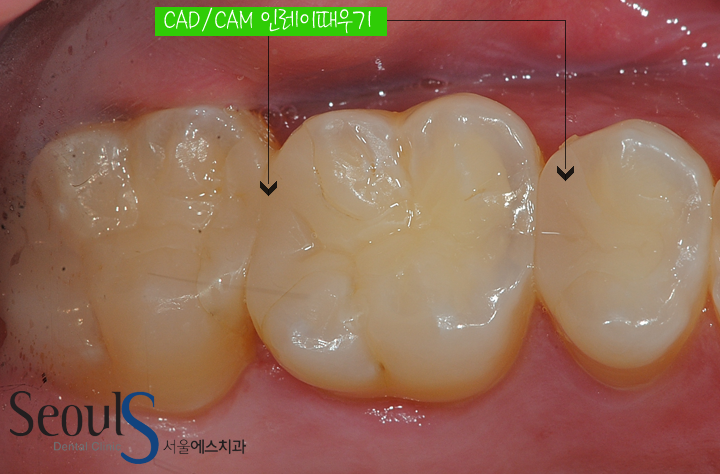

이제 빈 공간에 딱맞는 CAD/CAM 인레이 제작 후 때워 치료를 마칠 예정입니다

CAD/CAM 인레이로 때워 치료를 마친 모습입니다

자연스럽고 예쁘게 치료된 모습입니다

치료 전후 모습입니다

충치 제거 후 캐드캠 인레이로 때웠습니다